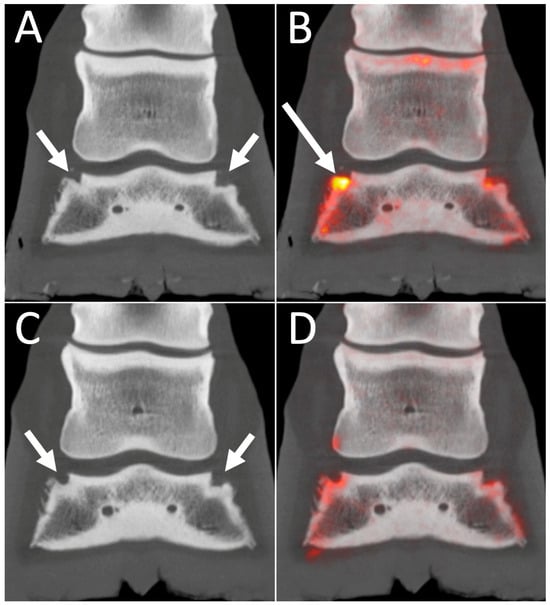

3.2. Scintigraphy Combined with CT and MRI

4.2. 18F-NaF PET Combined with CT or MRI for Optimal Bone Imaging